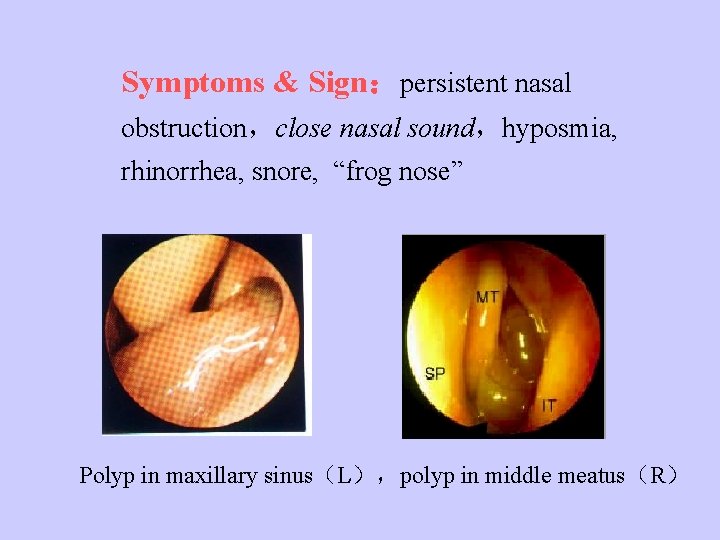

Symptoms & Sign:persistent nasal obstruction,close nasal sound,hyposmia, rhinorrhea, snore, “frog nose” Polyp in maxillary sinus(L),polyp in middle meatus(R)